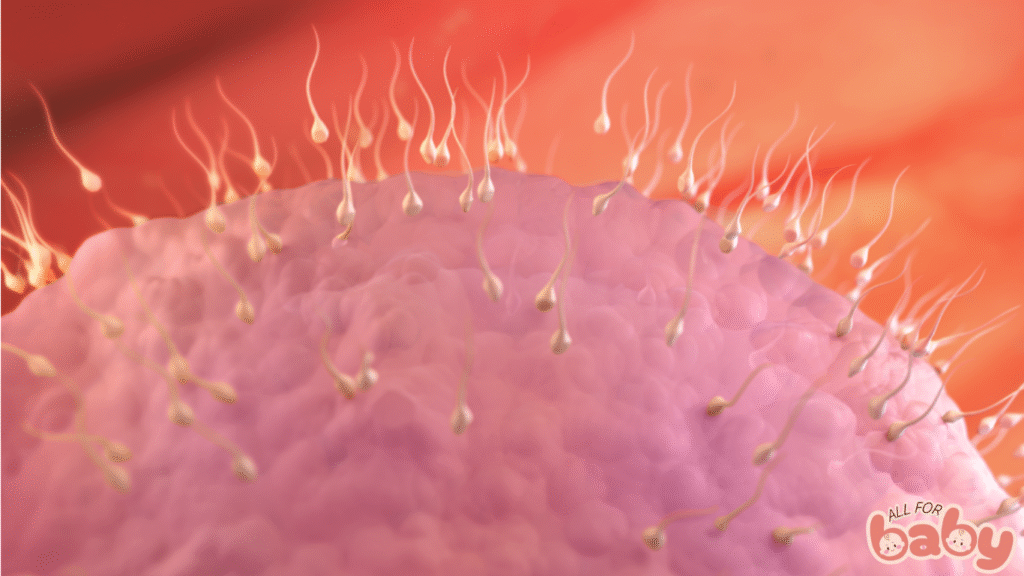

Ở tuần 2, thực tế mẹ chưa thực sự mang thai. Thai kỳ được tính từ ngày đầu tiên của kỳ kinh cuối cùng, vì vậy tuần này chủ yếu là giai đoạn rụng trứng.

Vào khoảng ngày 14 của chu kỳ kinh 28 ngày, buồng trứng sẽ phóng thích một trứng trưởng thành.

Nếu trứng gặp được tinh trùng trong ống dẫn trứng, quá trình thụ tinh sẽ xảy ra và tạo thành hợp tử.

Hợp tử này sẽ bắt đầu di chuyển về tử cung để chuẩn bị làm tổ ở tuần kế tiếp.